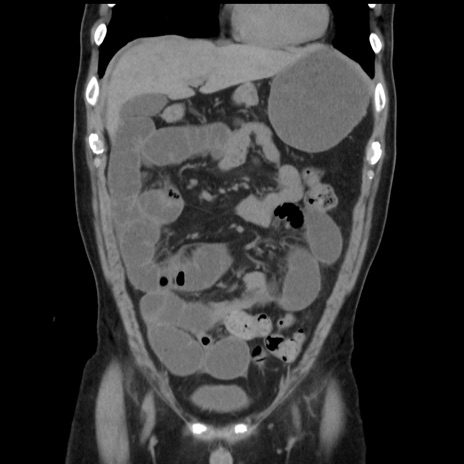

症例16(冠状断像)

【症例】 70歳代男性

【主訴】 腹痛、嘔吐

【現病歴】 約1ヶ月前より間欠的に腹痛と嘔吐あり、当院消化器内科を受診したところCTで多発する肝臓のLDAを指摘され、精査中であった。以降は消化器症状は安定していたが、2日前より嘔気と腹痛があり、同日より排便・排ガスが消失した。改善認めず、 本日、救急外来を受診した。

【既往歴】 大腸ポリープ切除後。

【身体所見】意識清明・会話良好、BT 36.3℃、BP 127/80mmHg、 P 80bpm、腹部:膨満あり、平坦・軟、上腹部正中および下腹部正中に圧痛あり、反跳痛なし、筋性防御なし。

【データ】WBC 7200、CRP 0.77

横断像